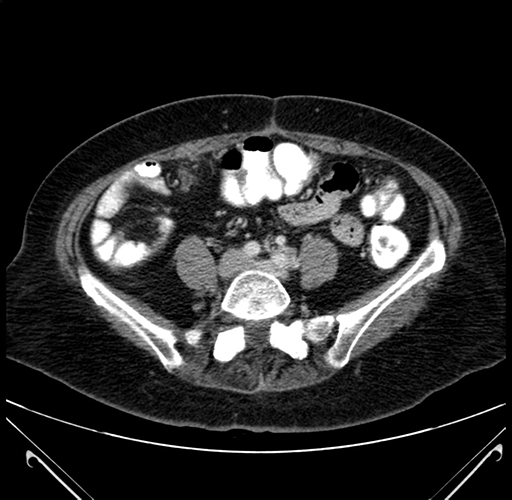

Axial Venous